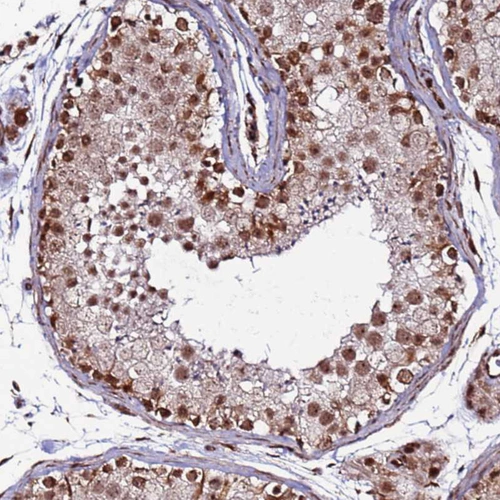

Immunohistochemical staining of human testis shows strong nuclear positivity in subset of cells in seminiferous ducts.